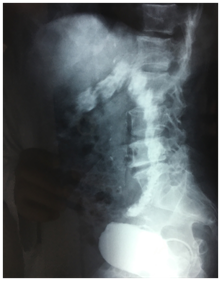

An antibiotherapy was started and retrograde and urinary uretro-cystography was performed. Retrograde cystography showed diverticular bladder with opacification of the sigmoid colon up to the half of the transverse colon (Figure 1) (Figure 2).

Figure 1 Frontal view of retrograde urethrocystography showing opacification of the sigmoid and descending colon.